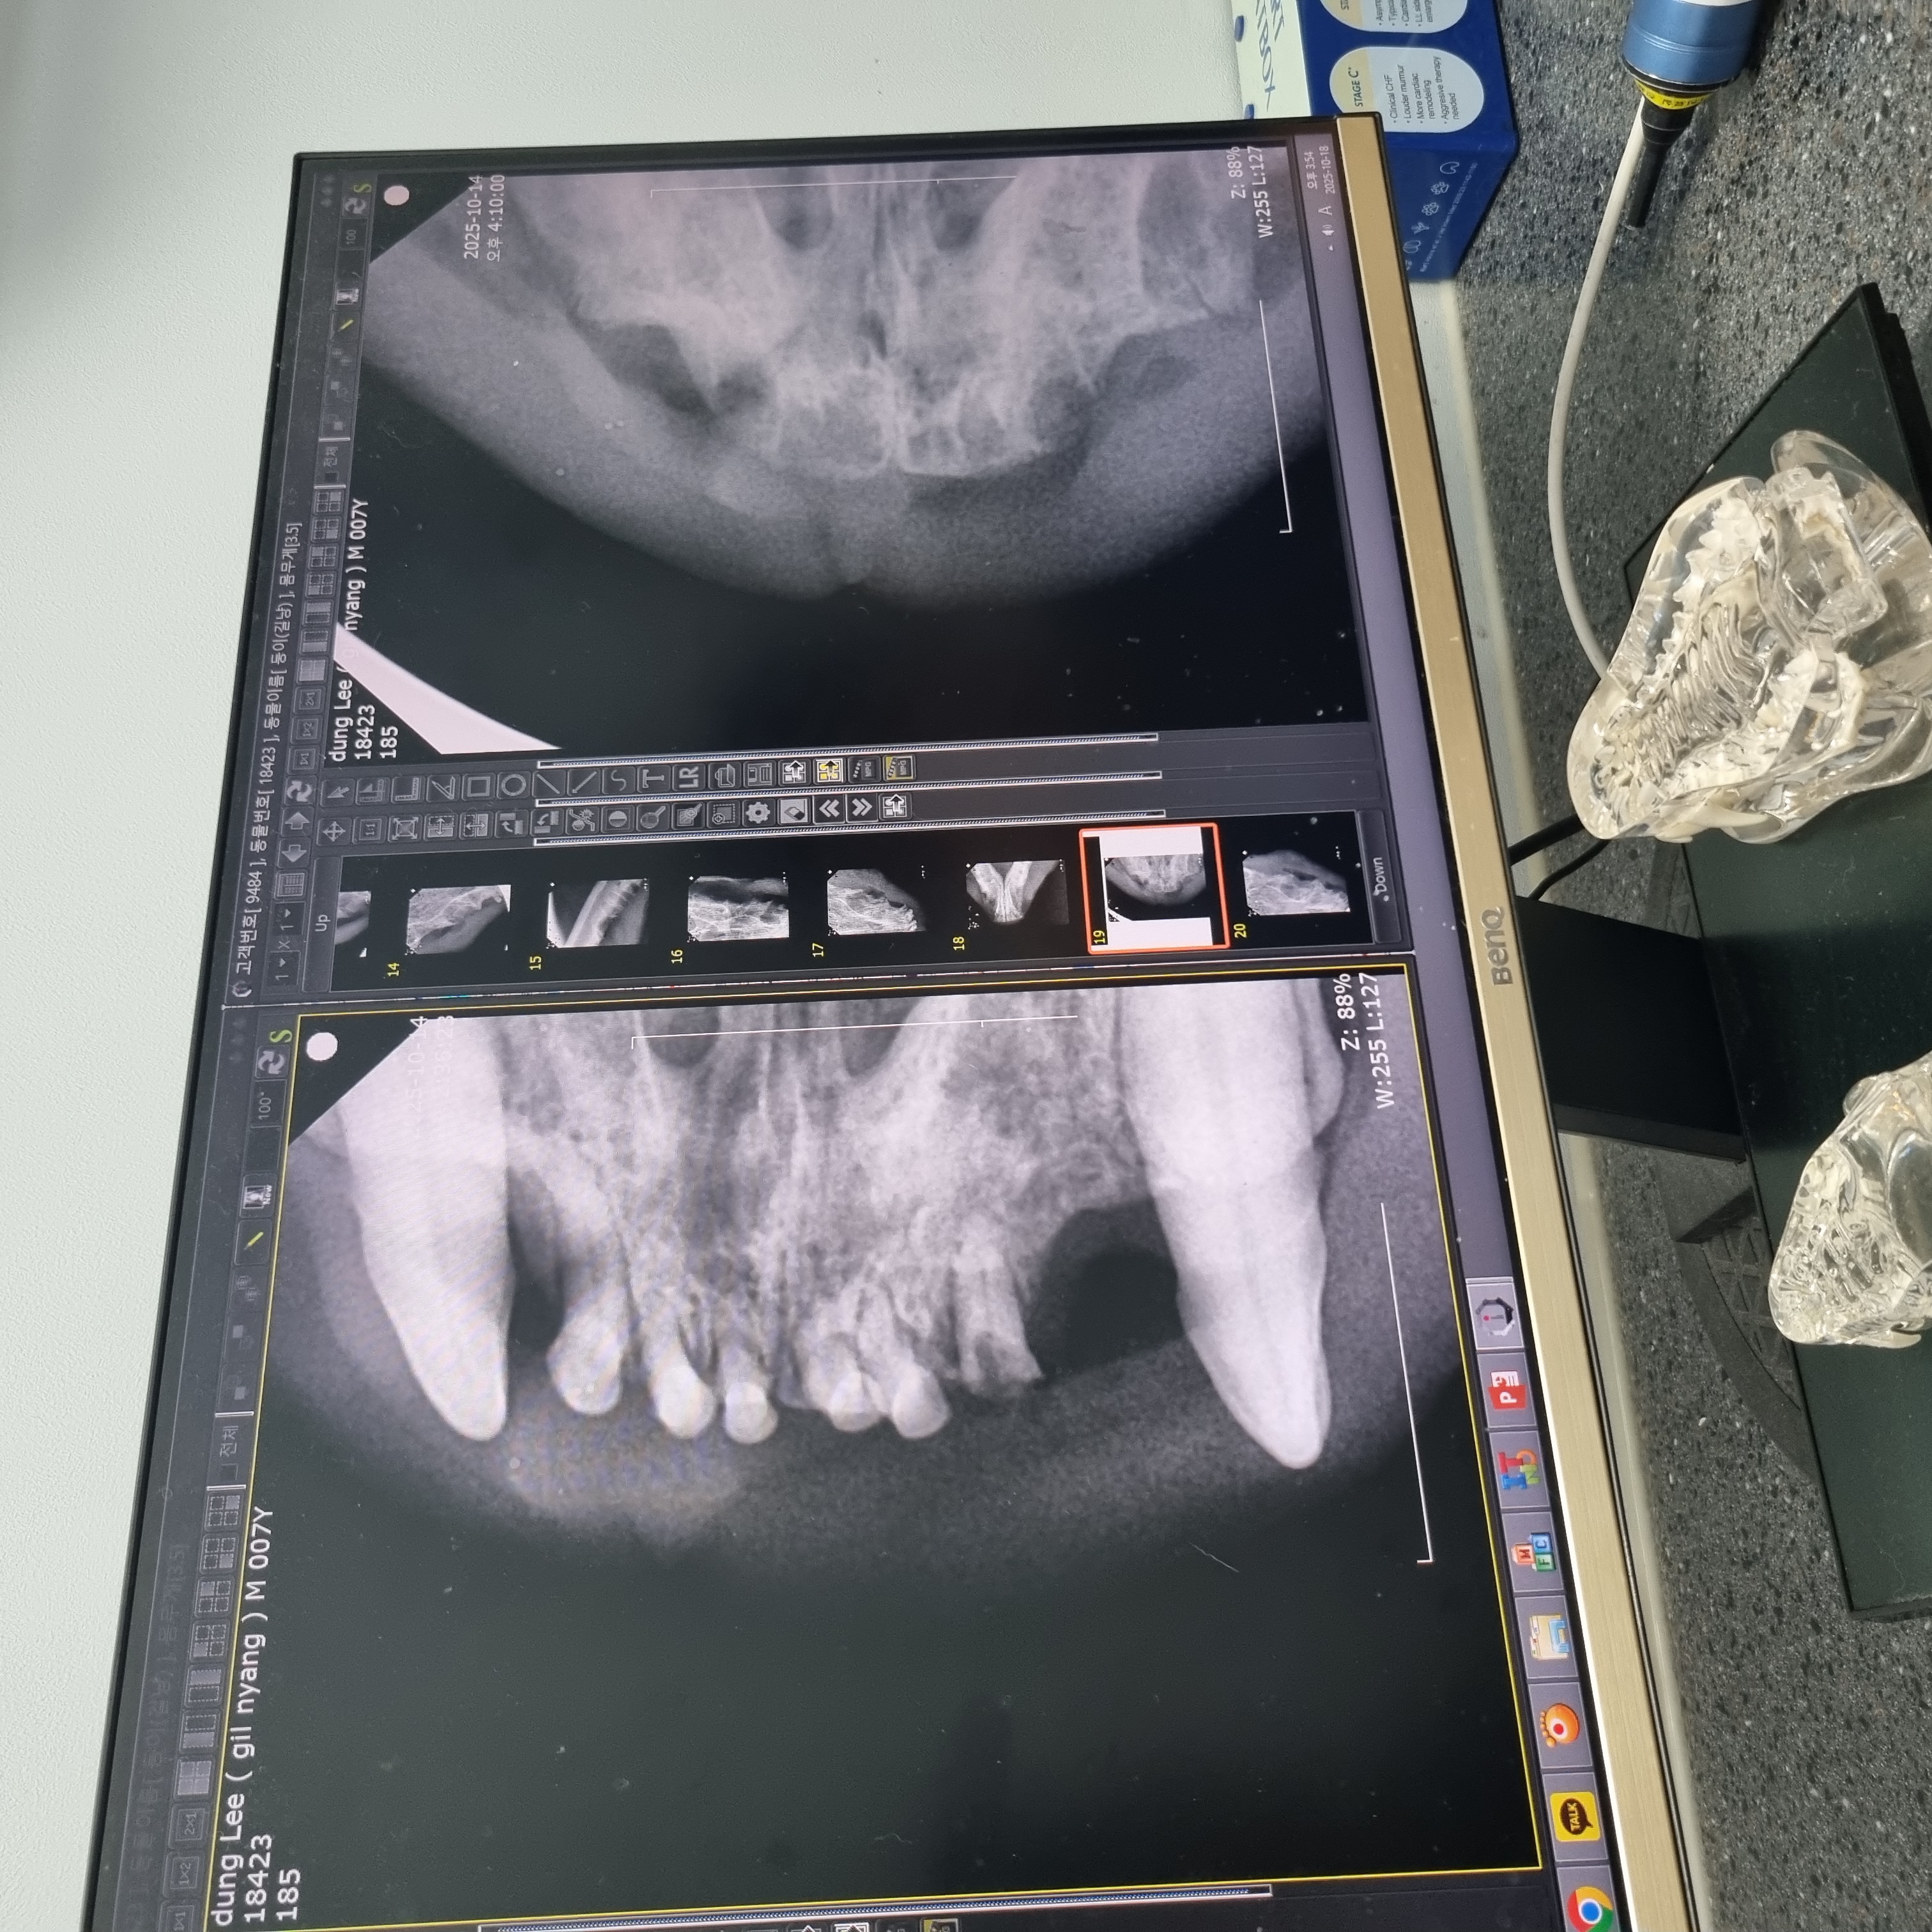

| 치료과정 | 츄르나 파우치를 먹을 때 아주 크게 왕!! 하고 짖는 등 고통을 호소하고 작년보다 최소 2~3킬로는 빠진 모습이라 급히 치료지원신청을 하였고 당일 둥이 구조에도 성공했습니다 둥이는 10월 4일에 구조하게 되었고 이후 병원에 내원하여 정확한 상태를 확인받았습니다. 우리 둥이 마취 후 입 안을 보니 전발치를 해야하는 아주 전형적인 증상이라고 사진을 보여주셨습니다. 둥이의 목구멍 주위에 동그랗고 빨갛게 부은 염증부터 삭아버린 이빨... 얼마나 고통스러웠을지 사진을 보고 마음이 너무 아팠어요. 둥이의 수술을 위해 혈액검사와 키트검사 등을 진행하고 전발치수술을 하게 되었습니다. 수술 이후에는 병원에서 송곳니까지 깨끗하게 전발치한 사진을 치아엑스레이를 찍어 상세하게 보여주셨습니다. 수술을 마친 이후에는 병원에 입원시켜서 수액 처치도 받고 회복에 전념하였습니다. 둥이는 며칠전에 면회때만 해도 좀처럼 기운이 없어 여러 걱정이 많았는데 다행히 어제 면회 때는 기력을 되찾은 모습입니다. 큰 소리로 야옹거리기도 하고 입원실 밖도 돌아다니고 먹고 아주 조금 남은 습식사료까지 싹싹 핥아먹는 모습을 보였습니다. |